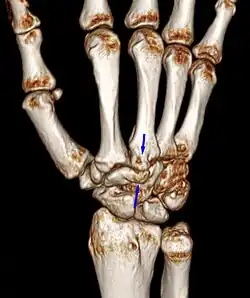

Carpal boss in plain X-Ray. Carpal boss in plain X-Ray.

Carpal boss in CT. Carpal boss in CT.